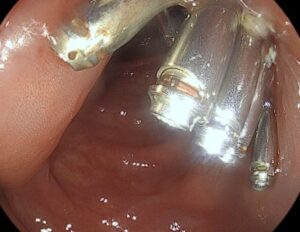

Εγκάρσιο :Επανελέγχεται η γνωστή επίπεδη πολυποειδής βλάβη διαμέτρου 4εκ., αφαιρέθηκε με βρόχο πολυπεκτομής μετά από υποβλεννογόνια έγχυση BluedeMethylene. Στη συνέχεια έγινε θερμοκαυτηριασμός στα ορατά αγγεία με Argon Plasma Coagulation (APC). Τοποθετήθηκαν 12 μεταλλικά αιμοστατικά clipsγια την σύγκλιση του ελλείματος και την αποφυγή μεταγενέστερης αιμορραγίας.